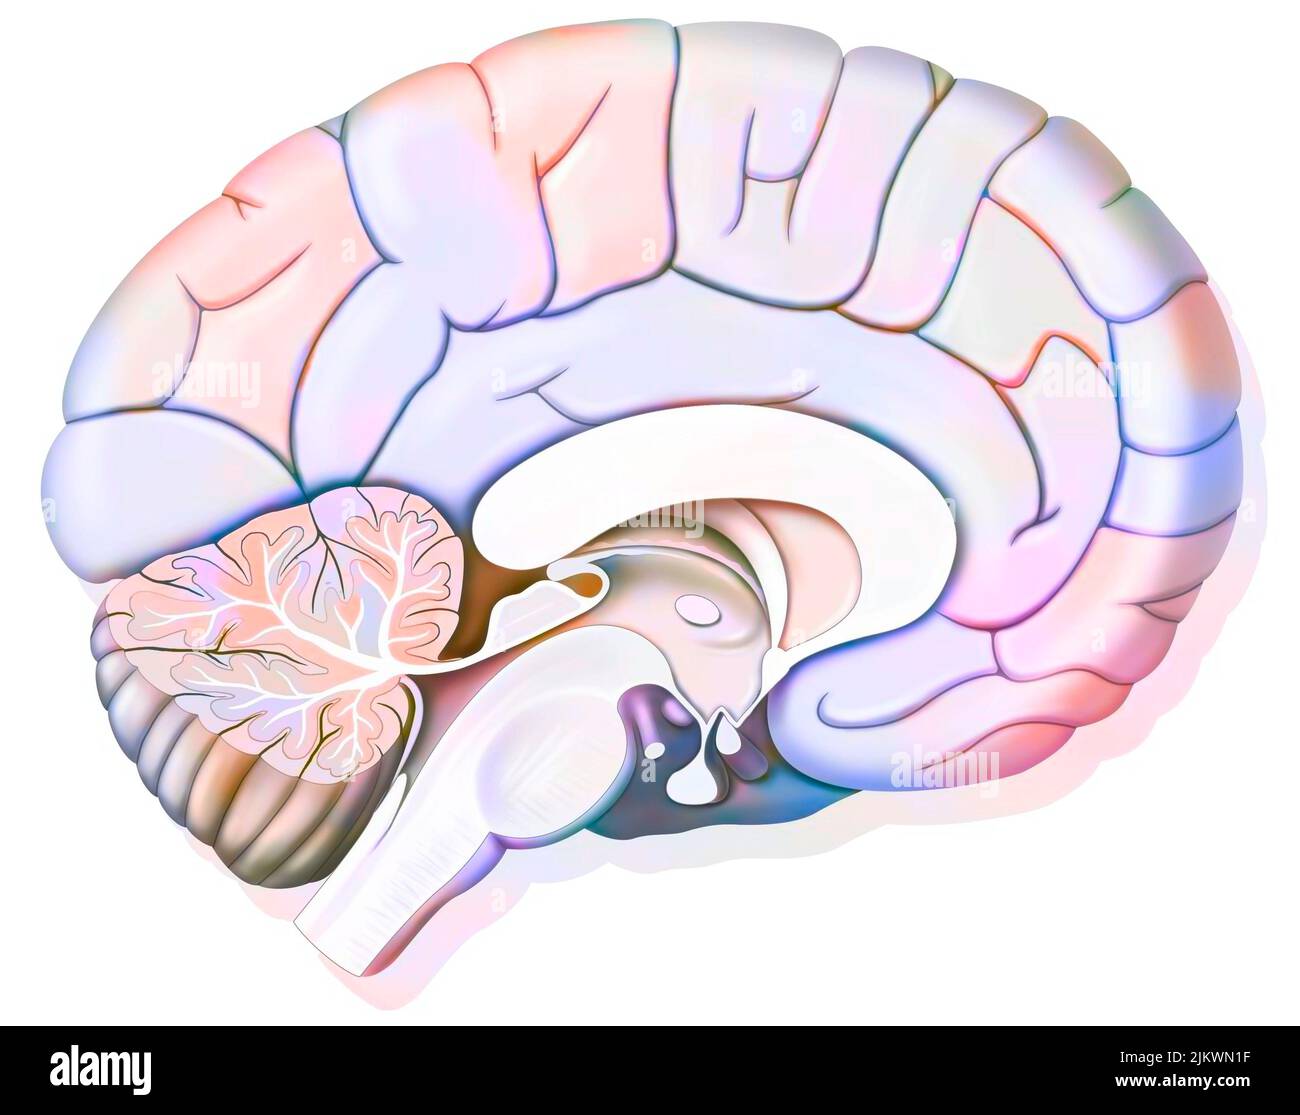

RF2JKWPG7–Troisième étape dans la façon dont le cerveau fonctionne quand vous tombez amoureux: La prise de décision.

RF2JKWPG3–Cerveau dans le chimpanzé avec ses zones (cognitives, auditives, visuelles) et cortex (moteurs, sensoriels).